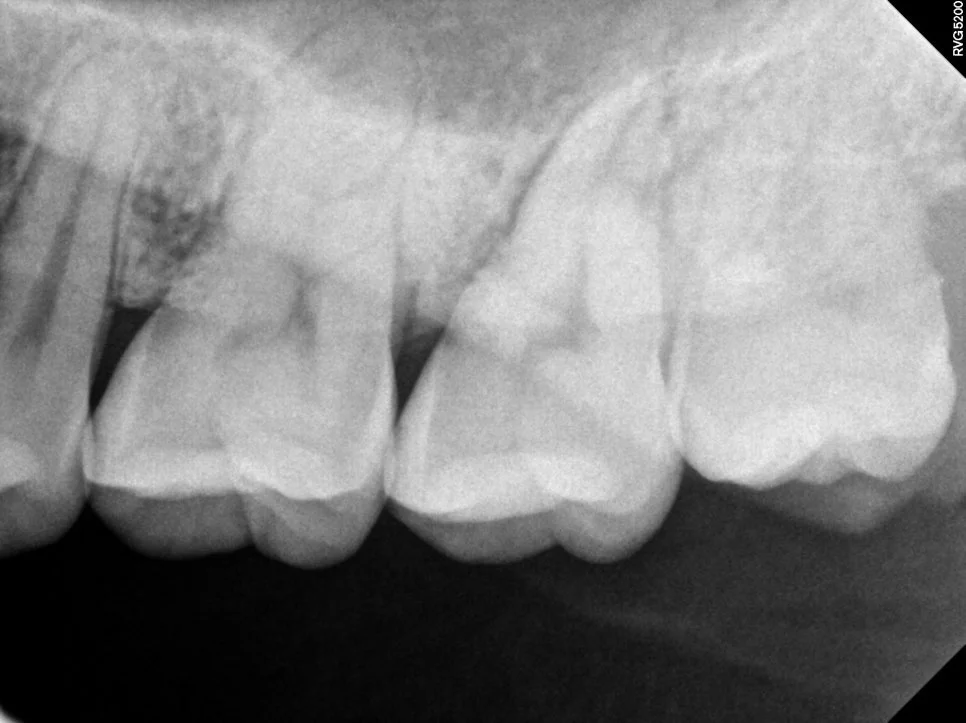

케이스2 우측 매복 사랑니 제2대구치 위협

우측 하악 매복 사랑니 — 제2대구치 바깥 면을 위협하는 가장 고난도 케이스

오른쪽 아래 매복 사랑니는 제2대구치의 바깥 면을 위협하고 있어 가장 난도가 높지만 빠르게 발치를 해줘야 하는 상태입니다.